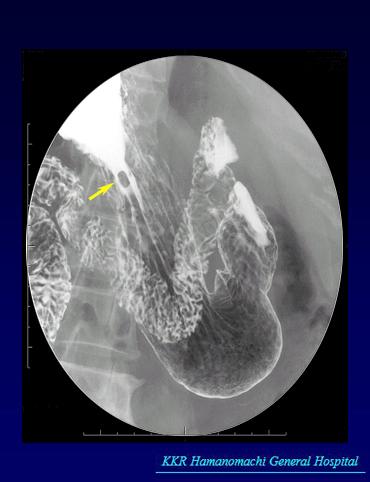

症例提示(所在地,施設名等): 福岡県・ 国家公務員共済組合連合会 浜の町病院 (松浦隆志先生からの提供症例)

疾患(病理主体)の分類カルチノイド腫瘍/

部位(臓器別)胃(部位)/2つ以上

検査方法X-P

病変の最大径(ミリ)1〜9

腫瘍の深達度sm

多発腫瘍(同一臓器)有(同時性)